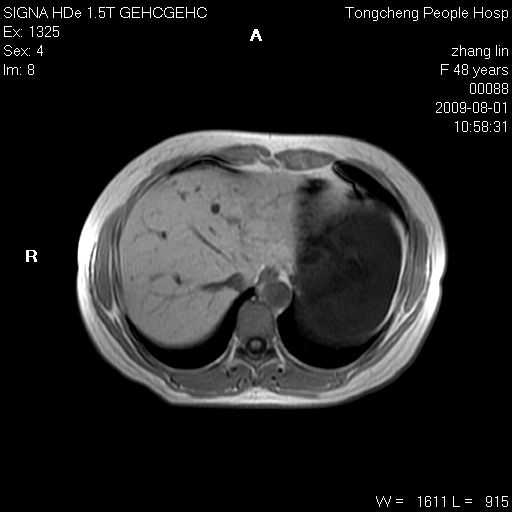

女,48岁。健康体检,彩超发现右肾占位性病变。平素健康。

临床诊断:右肾占位性病变,性质待定(囊肿?肿瘤?)。

上中腹部mr平扫+增强扫描,图像如下:

右肾上极见一类圆形病灶,t1wi呈等信号t2wi呈等高混杂信号,三期增强无强化,边界清---考虑囊肿出血。

同反相位均表现为等信号,病变无强化,考虑含蛋白的囊肿可能,弥散加权相或许有些帮助,